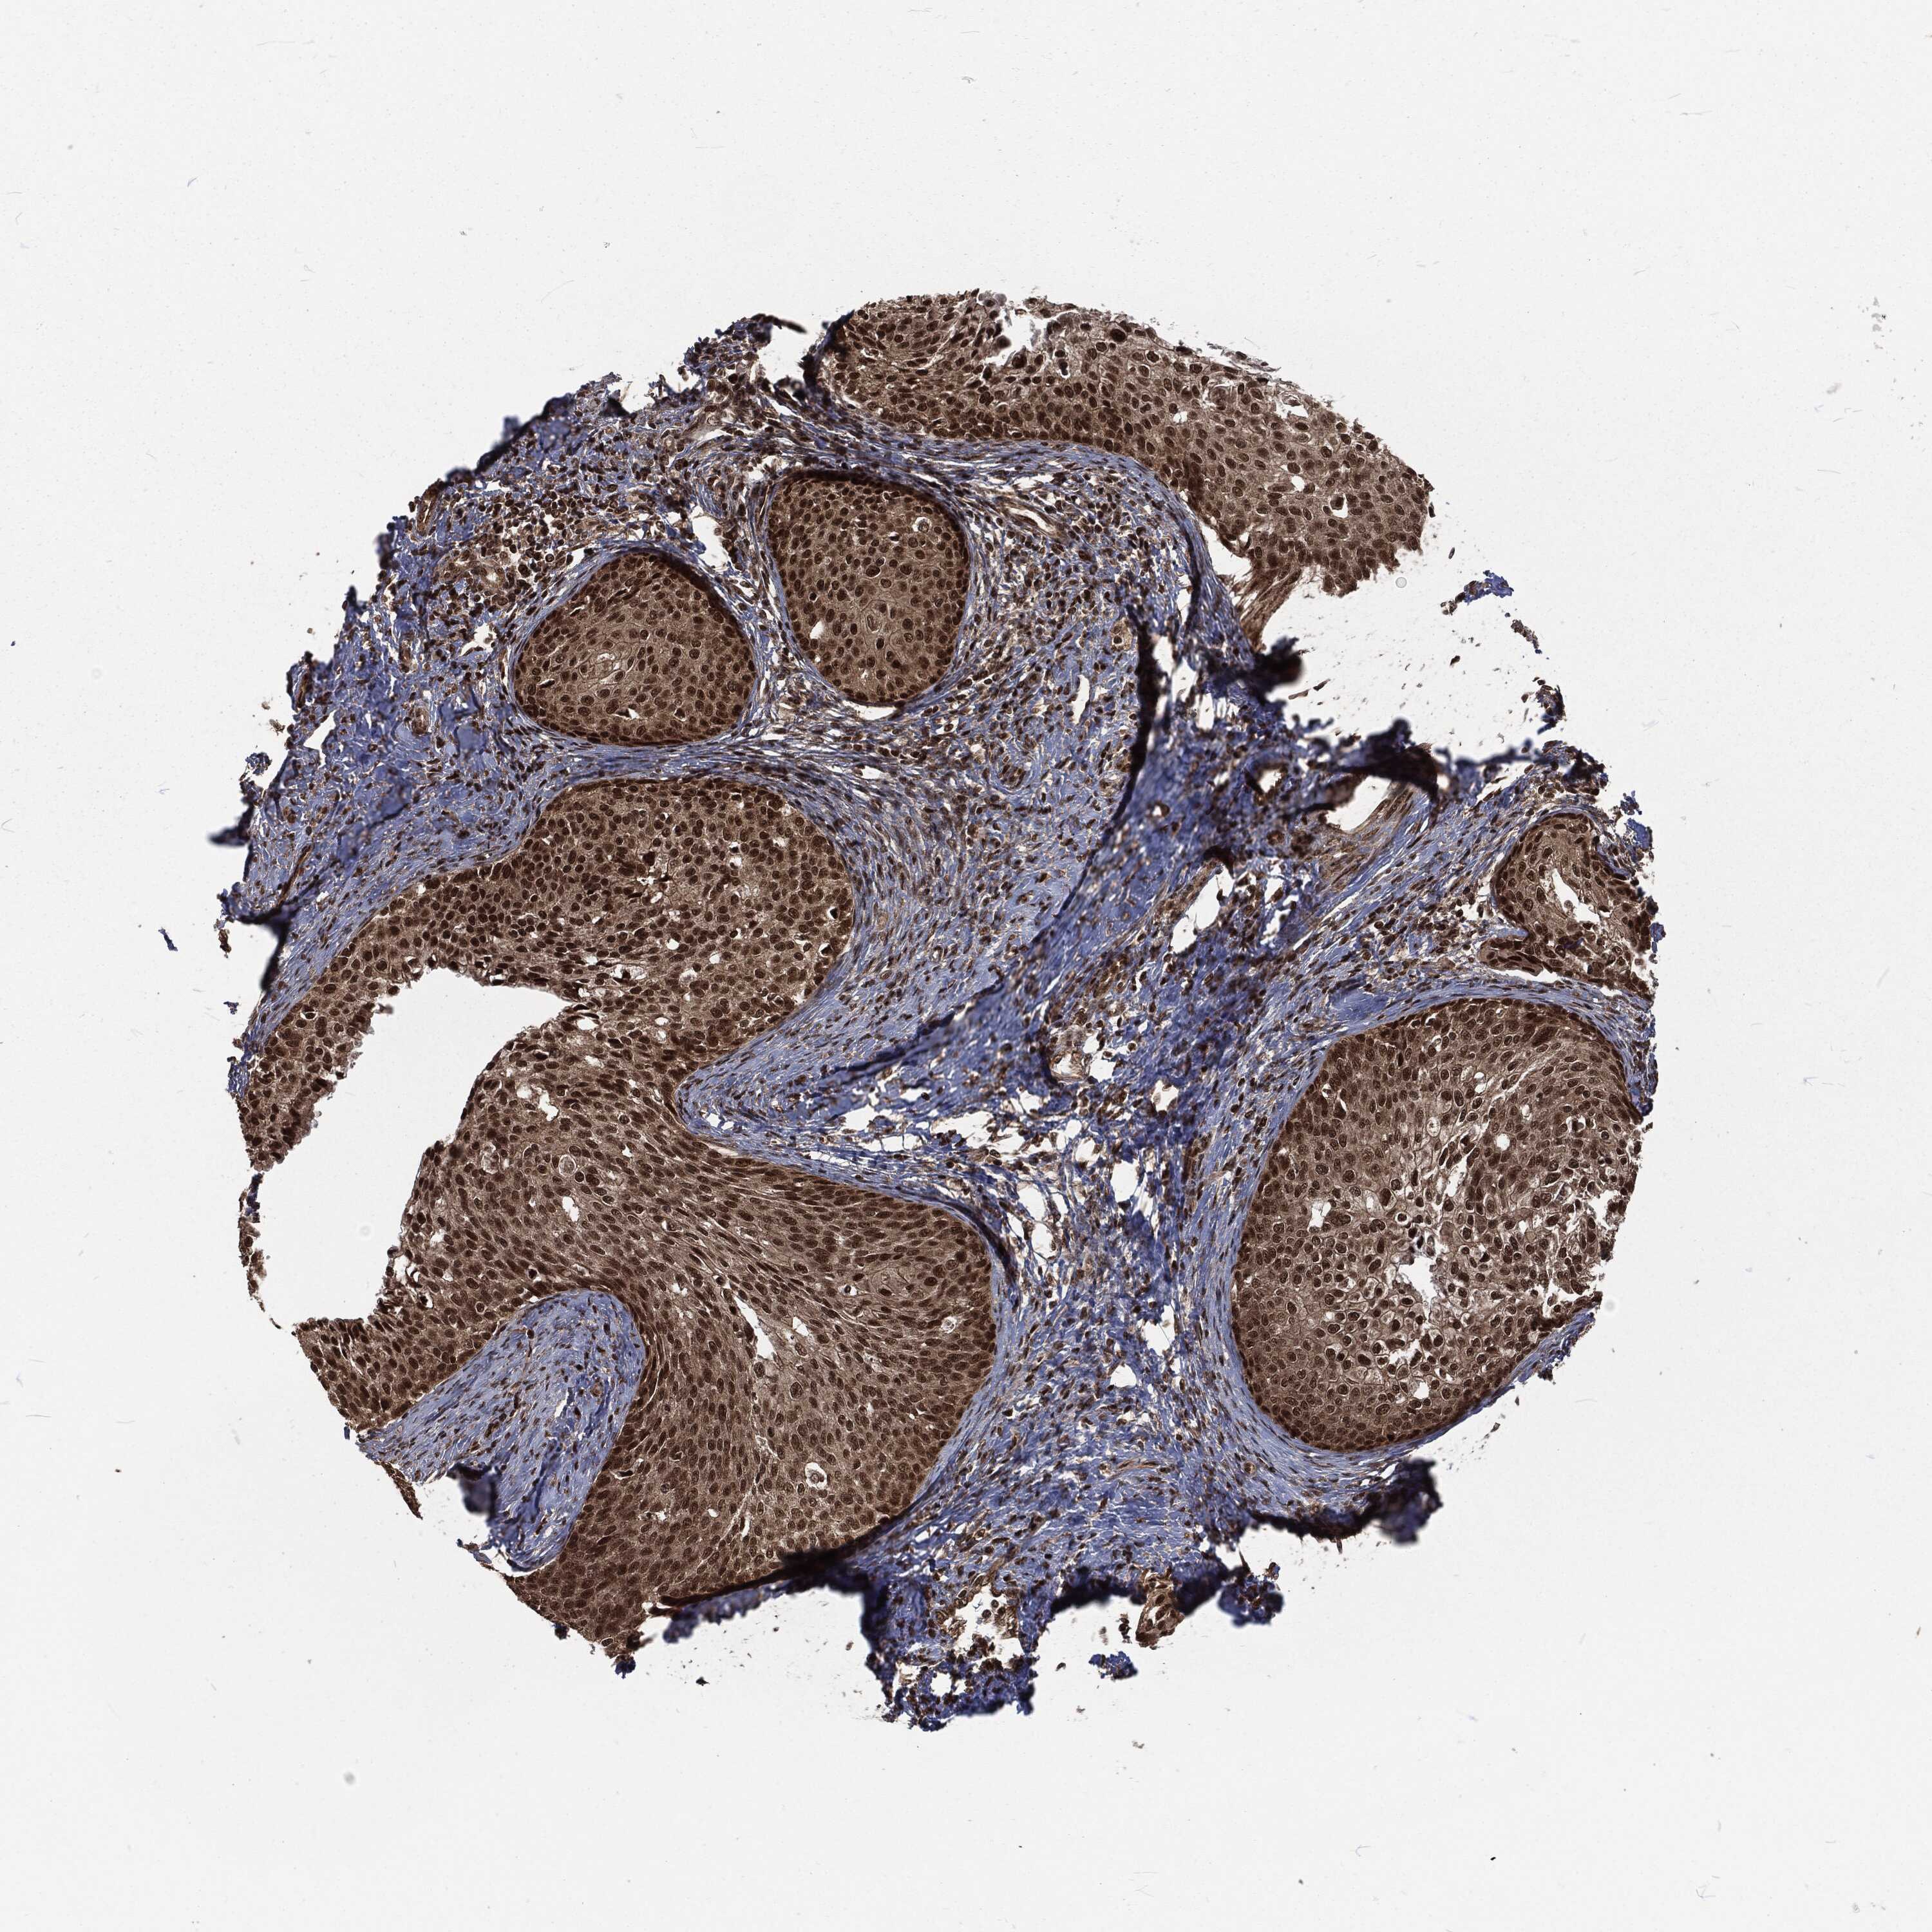

CERVICAL CANCER - Protein expressioni

A mouse-over function shows sample information and annotation data. Click on an image to view it in a full screen mode. Samples can be filtered based on level of antibody staining by selecting one or several of the following categories: high, medium, low and not detected. The assay and annotation is described here.

Note that samples used for immunohistochemistry by the Human Protein Atlas do not correspond to samples in the TCGA dataset.

Antibody stainingi

Antibody staining in the annotated cell types in the current human tissue is reported as not detected, low, medium, or high, based on conventional immunohistochemistry profiling in selected tissues. This score is based on the combination of the staining intensity and fraction of stained cells.

Each image is clickable and will lead to virtual microscopy that enables deeper exploration of all samples and also displays staining intensity scores, fraction scores and subcellular localization as well as patient and tissue information for each sample.

Antibody HPA041367

Antibody HPA076267

Staining

High

Medium

Low

Not detected

Intensity

Strong

Moderate

Weak

Negative

Quantity

>75%

75%-25%

<25%

None

Location

Nuclear

Cytoplasmic/membranous

Cytoplasmic/membranous,nuclear

Squamous cell carcinoma, NOS

Adenocarcinoma, NOS